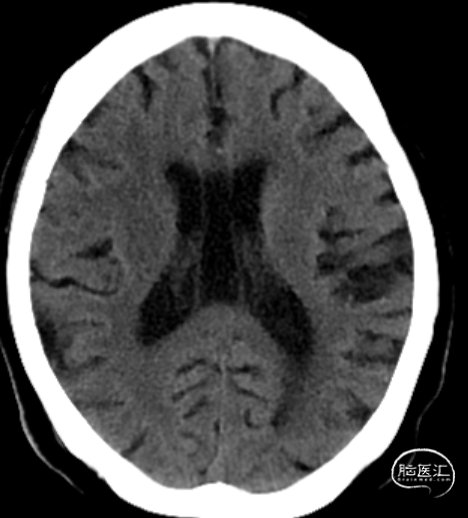

术前影像学检查

头颅CT平扫:右侧尾状核低密度灶。

ASPECTS:3分